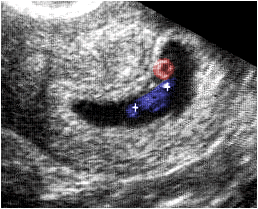

Ecografía obstétrica que muestra, la imagen de un embrión de 56 días de gestación (azul). Las marcas indican la longitud céfalo-caudal, cuyo valor es de 28 mm. La zona econegativa (rojo) corresponde al saco vitelino.